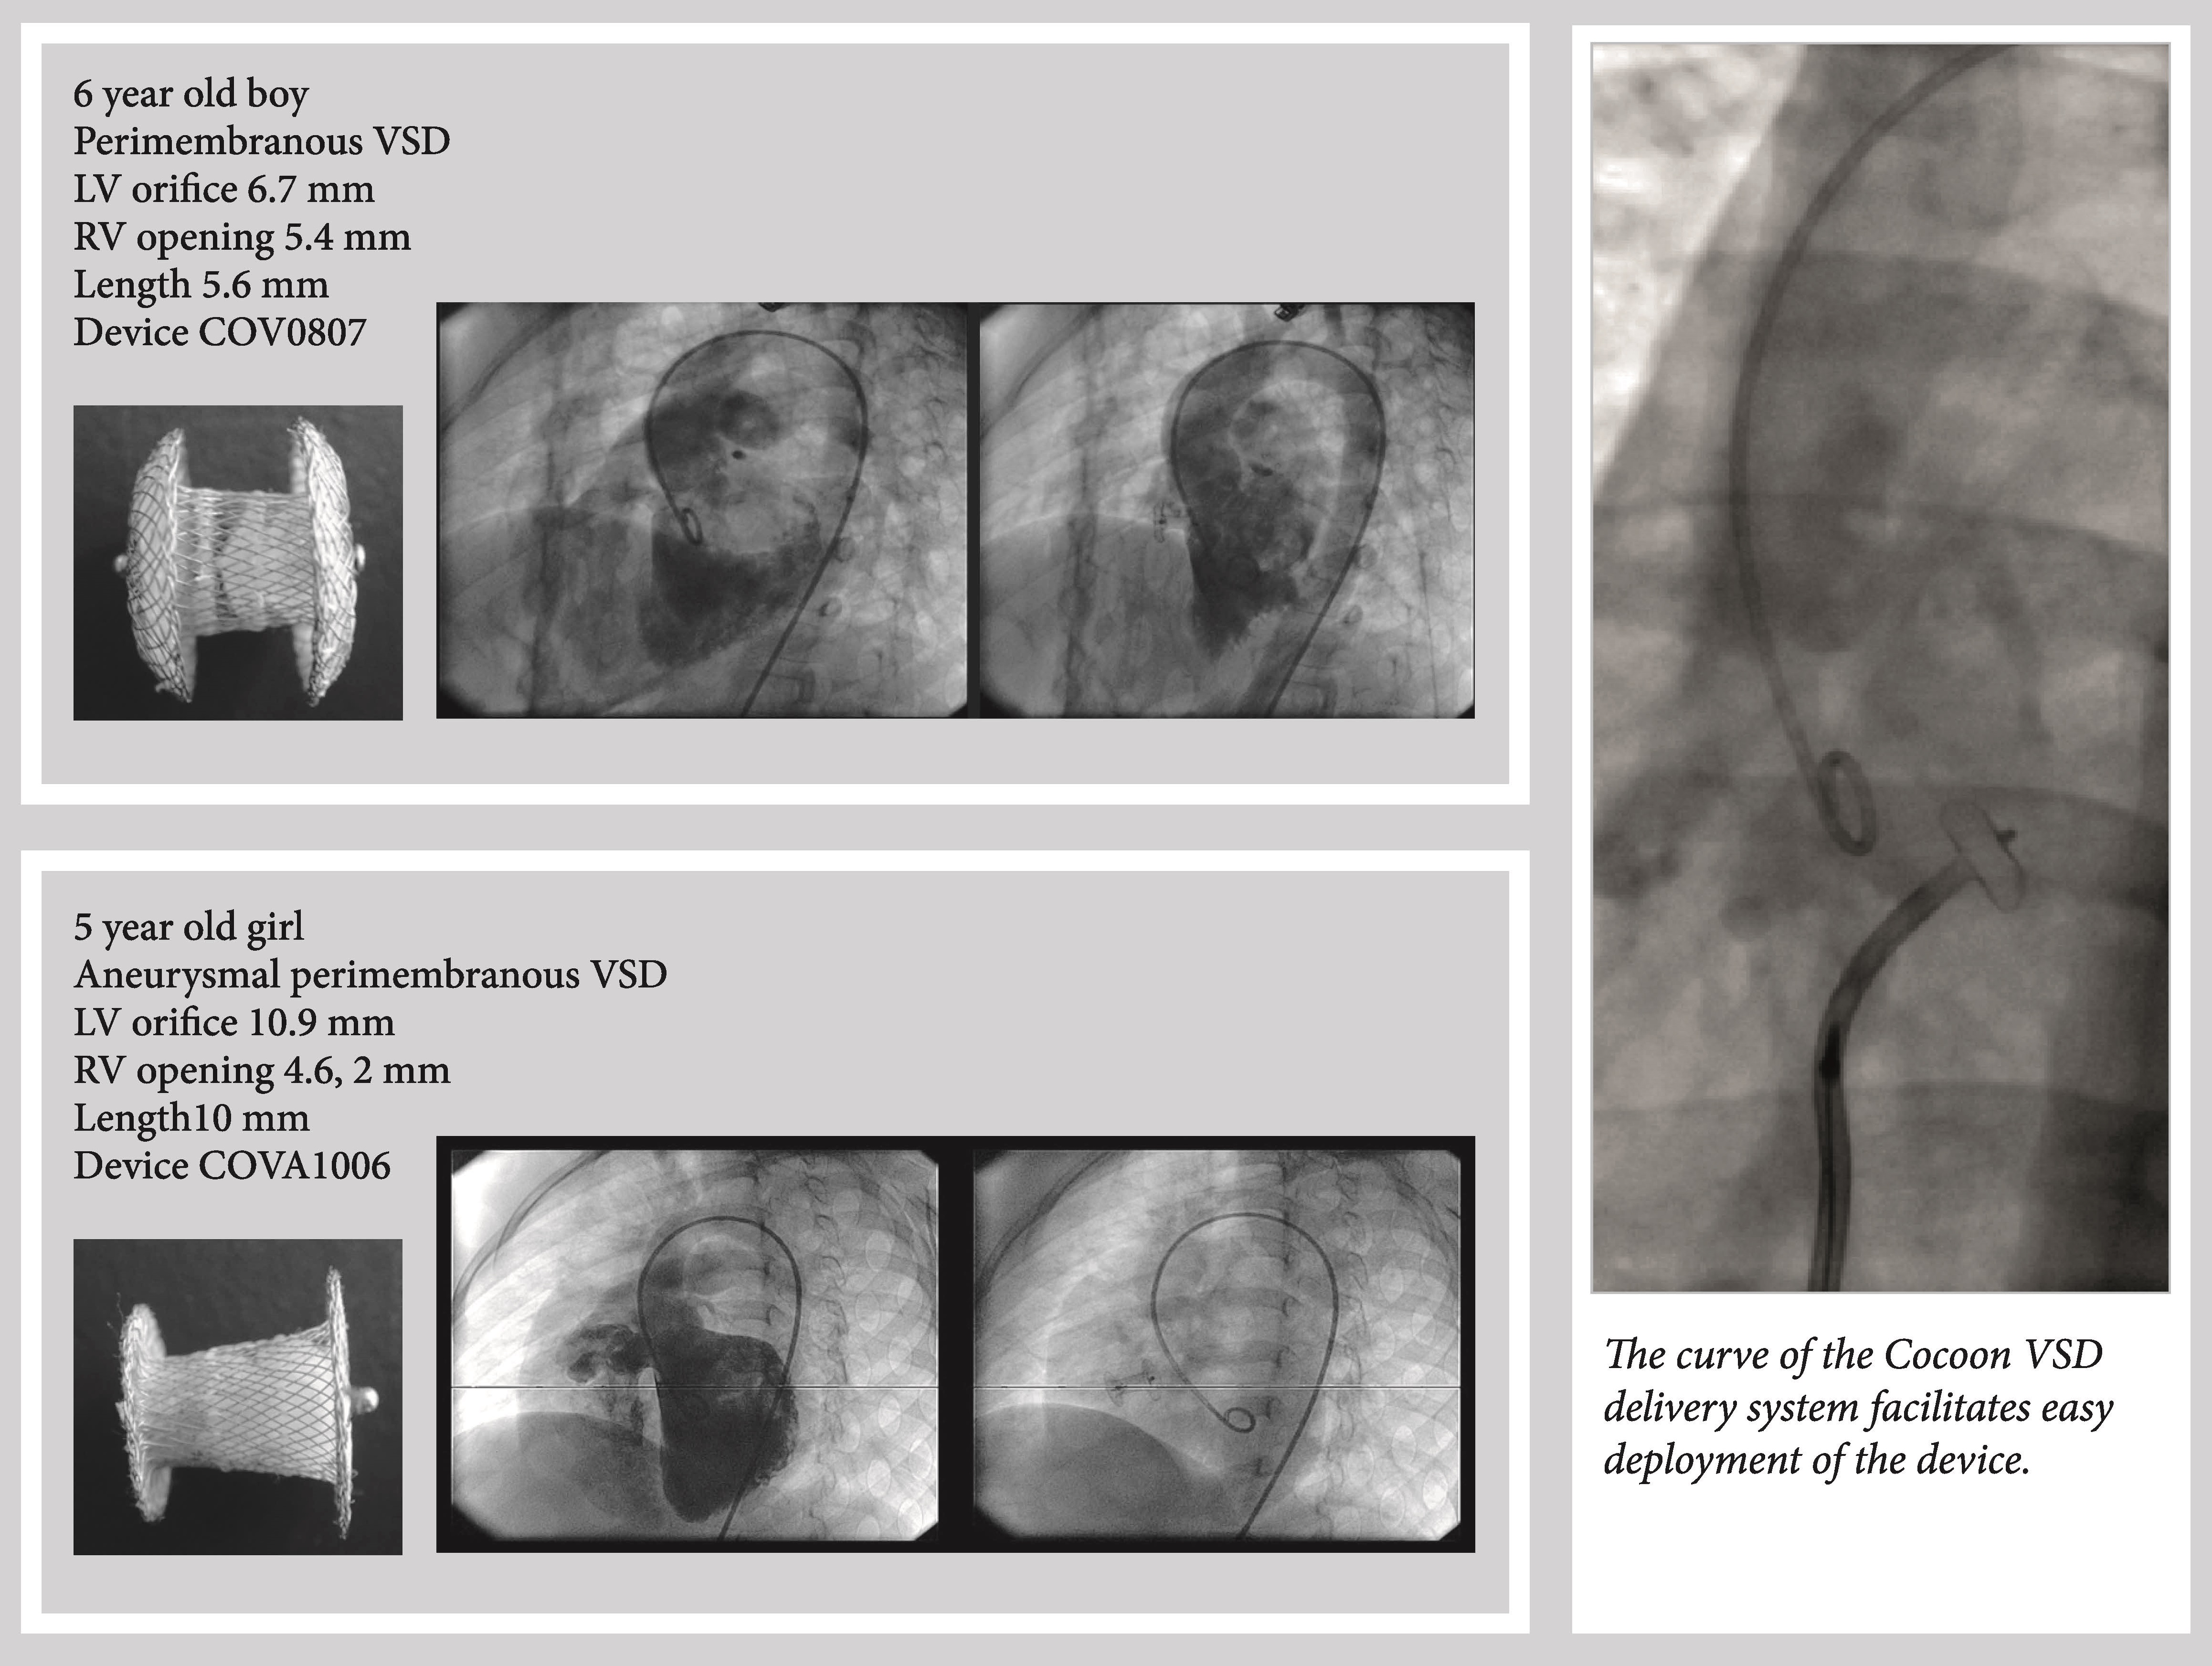

The Cocoon VSD Occluder is a self expandable double disk device manufactured from braided Nitinol wires coated with platinum. The two discs are linked together by a connecting waist and the waist diameter is corresponding to the defect size. Platinum provides superior biocompatible properties compared to Nitinol. The platinum coating also provides radio opacity which enables easy positioning in the defect. The discs are filled with polypropylene fabric which aids in total occlusion of defect.